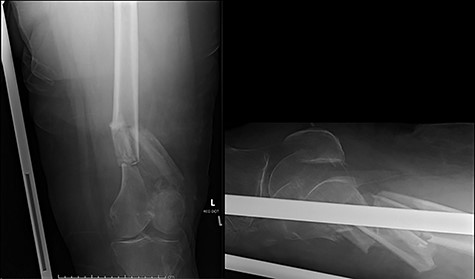

Case 2 (Figs 3–5): here difficulties were clearly encountered in achieving satisfactory reduction in the coronal plane. The screw immediately proximal to the fracture line is too close to the fracture.

Selecting a longer plate would have allowed proximal screws to sit more appropriately in order to reduce the risk of plate fatigue.